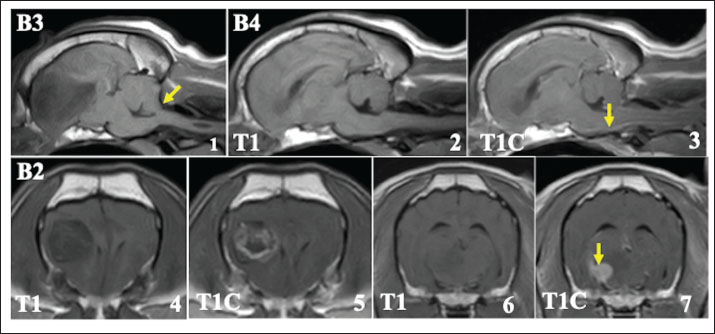

Radiotherapy improved the clinical symptoms of all patients who completed treatment, completing the radiotherapy schedule. In 7 cases with persistent seizure, antiepileptic medication was continued during and after radiotherapy. However, locomotor dysfunctions, such as ataxia and compulsive walking, improved in all 11 cases. MRI examinations performed after the final dose showed regression of primary tumor tissues in all cases (Fig. 2). In 7 cases, tumor tissue completely disappeared on MRI, and in the other 4 cases, showed apparent reductions and in tumor size as measured on MRI images. In all cases, CT evaluations of the thoracic and abdominal cavities performed with the last dose of the radiotherapy showed no distant metastatic lesions. At the end of radiotherapy, all patients were in an acceptable physical condition.

Fig. 2. The effect of radiotherapy on primary brain tumors in FBs. 1, 3: MRI findings before irradiation (contrast-enhanced T1-weighted image). 2, 4: MRI findings immediately after the final fraction of radiotherapy (contrast-enhanced T1-weighted image). Tumor tissue almost disappeared on MRI after radiotherapy.